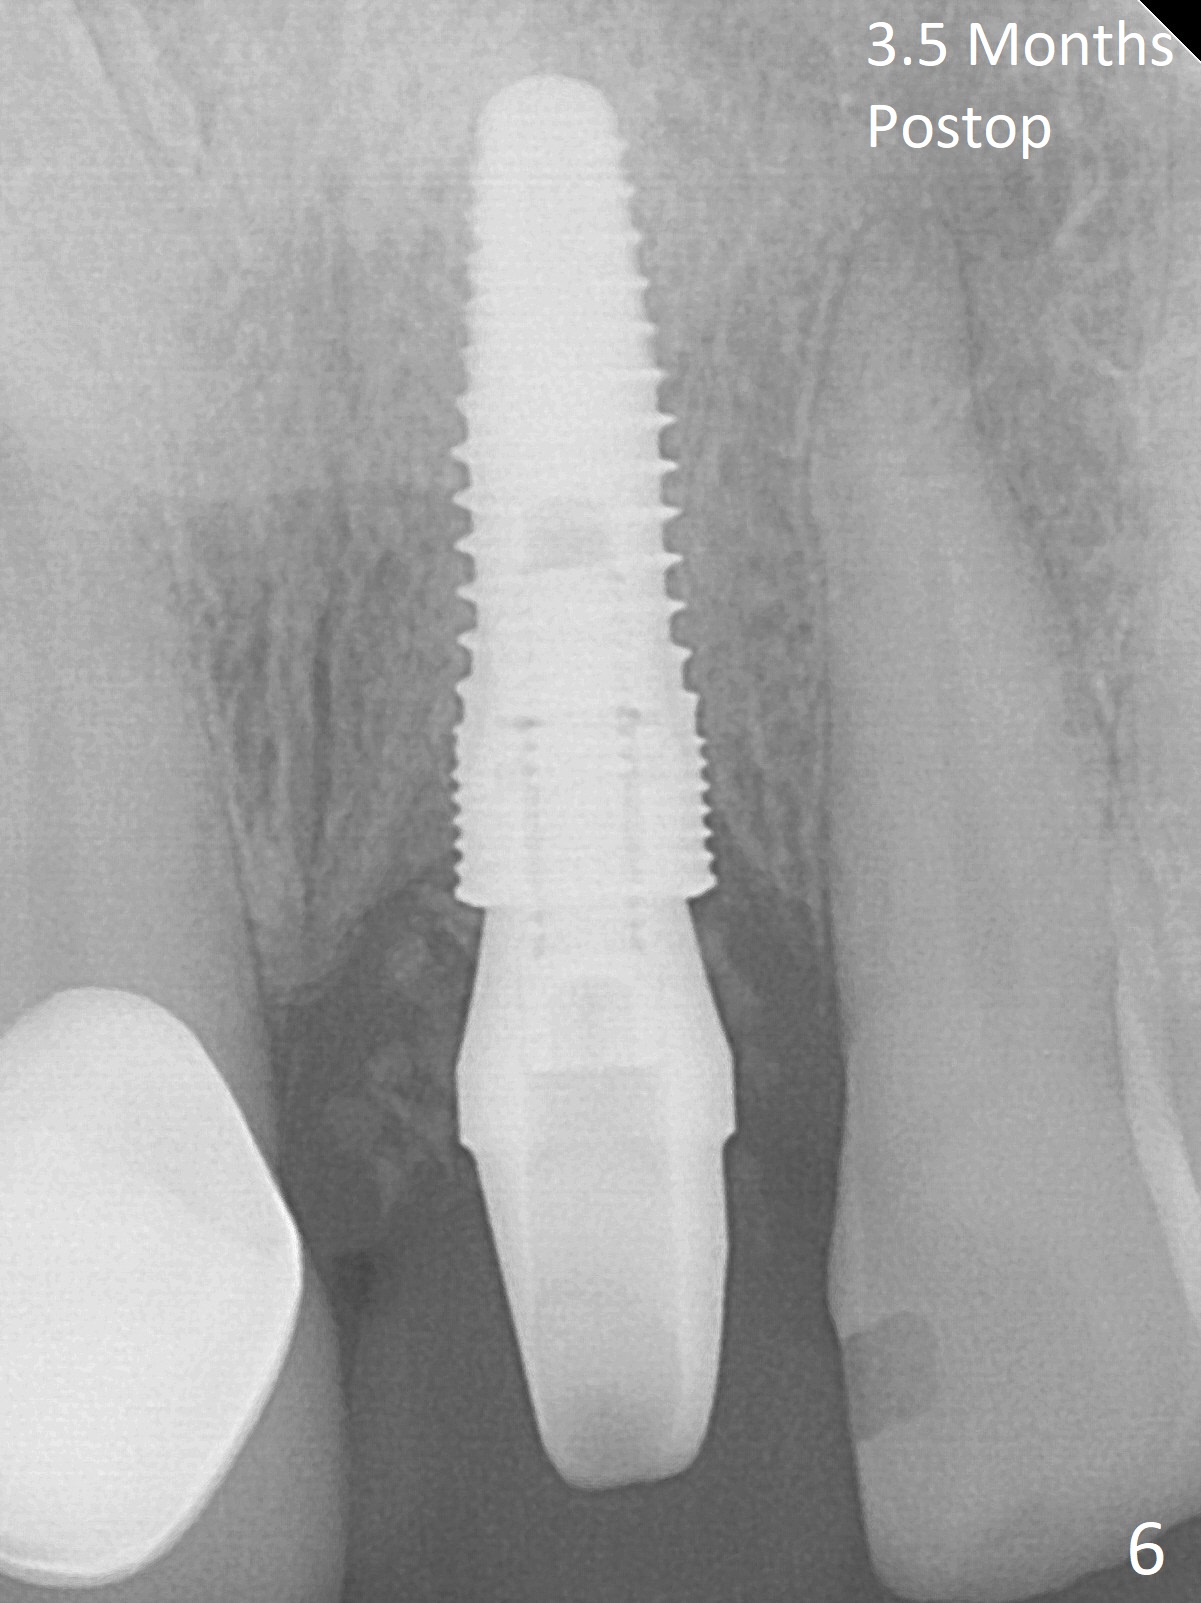

The buccal plate at #9 remains intact in spite of difficult extraction. Osteotomy is initiated in the palatal slope of the socket (Fig.1). The latter looks large when osteotomy is finished for a 3.8 mm implant. Without further osteotomy, a 4.5x14 mm SM implant is placed with primary stability (Fig.2). Without much attention, the coronal end of the bone-level implant is gradually deviated buccal, although the buccal gap is still 2 mm. An angled abutment is used (Fig.2); the future access hole is also buccal. Screw retention is impossible for cosmetic reason (Fig.3). To keep the access incisal and palatal, keep removing palatal bone sequentially. Or start osteotomy in the mid point of the palatal slope and keep the coronal end of the trajectory (Fig.5 pink line) palatal to the imagined incisal edge (Fig.4 white outline). The implant should be small (3.5 mm instead of 4.5 mm) so that it is easy to change the trajectory. The bone graft seems to have disappeared 3.5 months postop; the implant appears to have not been placed deep enough (Fig.6). In fact the implant plateau is < 2 mm subgingival palatal. An anterior immediate implant should be placed deep to reduce periimplantitis. There is reduced risk associated with abutment screw loosening, as compared to the posterior. Luckily the patient has used water pik since implant placement. On the other hand, water pik may be related to loss of bone graft. Therefore, water pik should be used 1 month post bone graft associated with immediate implant. The bone graft remains around the abutment cuff 4 months postop (Fig.7; immediately post cementation).